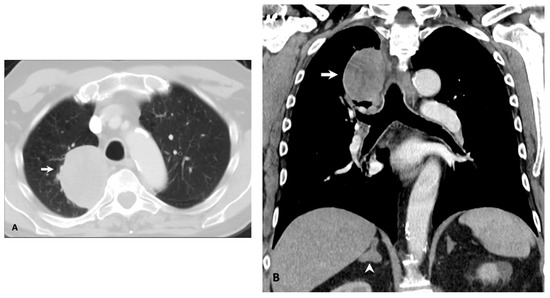

2.3. Metastatic Patterns